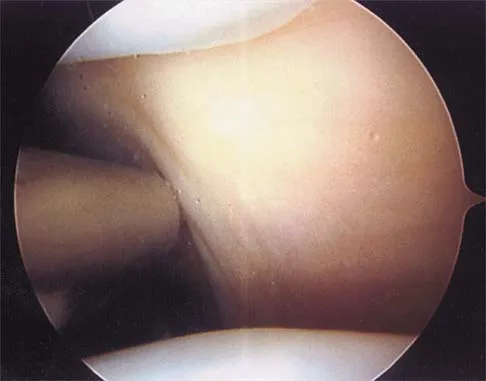

Figure 4a shows the radiograph of a 20-year-old man who has an injury to the right shoulder. Figure 4b shows an arthroscopic view (posterior portal). The arrow points to a

Explanation

The radiograph shows an anterior dislocation of the shoulder. A frequently encountered sequela of this is a compression fracture of the posterolateral humeral head, commonly referred to as a Hill-Sachs defect. The arthroscopic view of the glenohumeral joint visualizes the posterior aspect of the humeral head. In the image, the area devoid of cartilage to the right is the bare area. The indentation seen to the left is a Hill-Sachs defect. Matsen FA, Thomas SC, Rockwood CA, et al: Glenohumeral instability, in Rockwood CA, Matsen FA (eds): The Shoulder, ed 2. Philadelphia, PA, WB Saunders, 1998, pp 611-754.